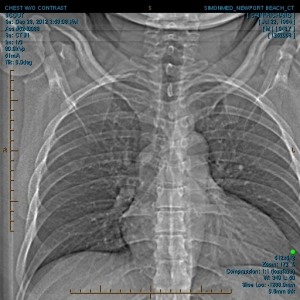

“My family and I have been the subjects of Government funded human research and/or hate crimes. These crimes are being covered-up by using the words National Security. The fact that my two minor children have the same and/or similar devices in their little bodies speaks for themselves. My sons were ages 3 and 4 when the discoveries took place. Their x-rays, blood & urine analysis present the true facts. The devices can only be introduced into the body, while being in a medical facility. All three of us were patient of the same defendant hospital.

“The CD-ROM from CCAI depicts the same images that are attached. I will bring the 01/03/2012 Simonmed Imaging CT scan which also depict foreign objets in the heart and chest.”

“Please take a look at both X-rays. Superimpose the foreign objects AKA EKG clamps and you will find that they are the same devices. when have you ever seen an EKG clamp place sideways in the abdomen? Both x-rays have been confirmed by Radiologist Louis Teresi as having foreign body reactions in the abdomen, right and left flanks.

“The obvious implant in the 2012 x-ray stands out from the others, because it at the time had not embedded into my flesh (heart).”